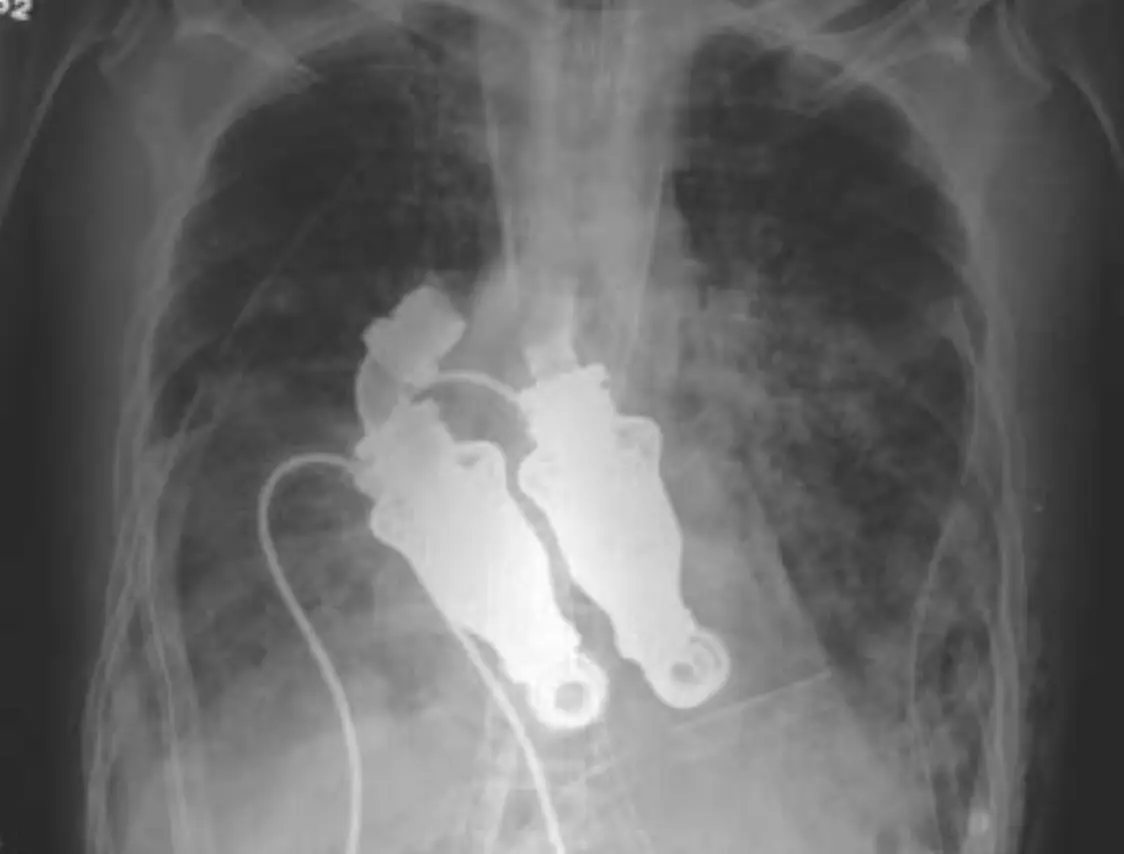

After decades of trial and error among surgeons desperately trying to create a machine that wouldn’t break down or cause blood clots and infections, two doctors at the Texas Heart Institute developed a device that used whirling rotors to pump blood around the body without a heartbeat.

Dr Billy Cohn and Dr Buz Frazier first tested the idea in an eight-month-old calf called Abigail, removing her heart and successfully replacing it with two centrifugal pumps, which circulated the blood through her.

After practicing on 38 calves, Cohn and Frazier progressed to human trials – selecting a 55-year-old man called Craig Lewis, who was suffering from amyloidosis, a rare autoimmune disease that causes a build-up of abnormal proteins and, in turn, rapid heart, kidney and liver failure.

In March 2011, she approached Cohn and Frazier, who removed her husband’s heart and installed the artificial device

She said her husband – who worked for the city of Houston, maintaining the city’s vast system of wastewater pumps – would have appreciated the pulseless heart cobbled together from various materials, with Cohn explaining: "Dacron on the inside and fiberglass impregnated in silicone on the outside.

"There's a moderate amount of homemade stuff on here."